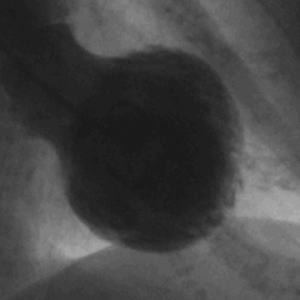

La cardiopatía de Takotsubo, también conocida como síndrome del corazón roto, es una condición clínica caracterizada por un debilitamiento temporal del músculo cardíaco que se presenta de manera aguda, y que se asocia frecuentemente con episodios de estrés emocional o físico intenso. Esta patología recibe su nombre debido a la forma del ventrículo izquierdo, que, al ser visualizado mediante técnicas de imagen como la ecocardiografía o la resonancia magnética, adopta una morfología similar a una olla japonesa utilizada para cocinar pulpos, conocida como «takotsubo». Esta imagen distintiva es consecuencia de la dilatación y la disfunción del ventrículo izquierdo, donde se produce un abultamiento significativo en la porción apical del corazón.

La cateterización cardíaca urgente es otro paso clave en el diagnóstico. Este procedimiento generalmente muestra un abultamiento en el área apical del ventrículo izquierdo, mientras que las coronarias suelen aparecer normales. Este hallazgo es crítico, ya que ayuda a diferenciar la cardiopatía de Takotsubo de un infarto de miocardio causado por enfermedad arterial coronaria, donde se esperaría ver obstrucciones significativas.